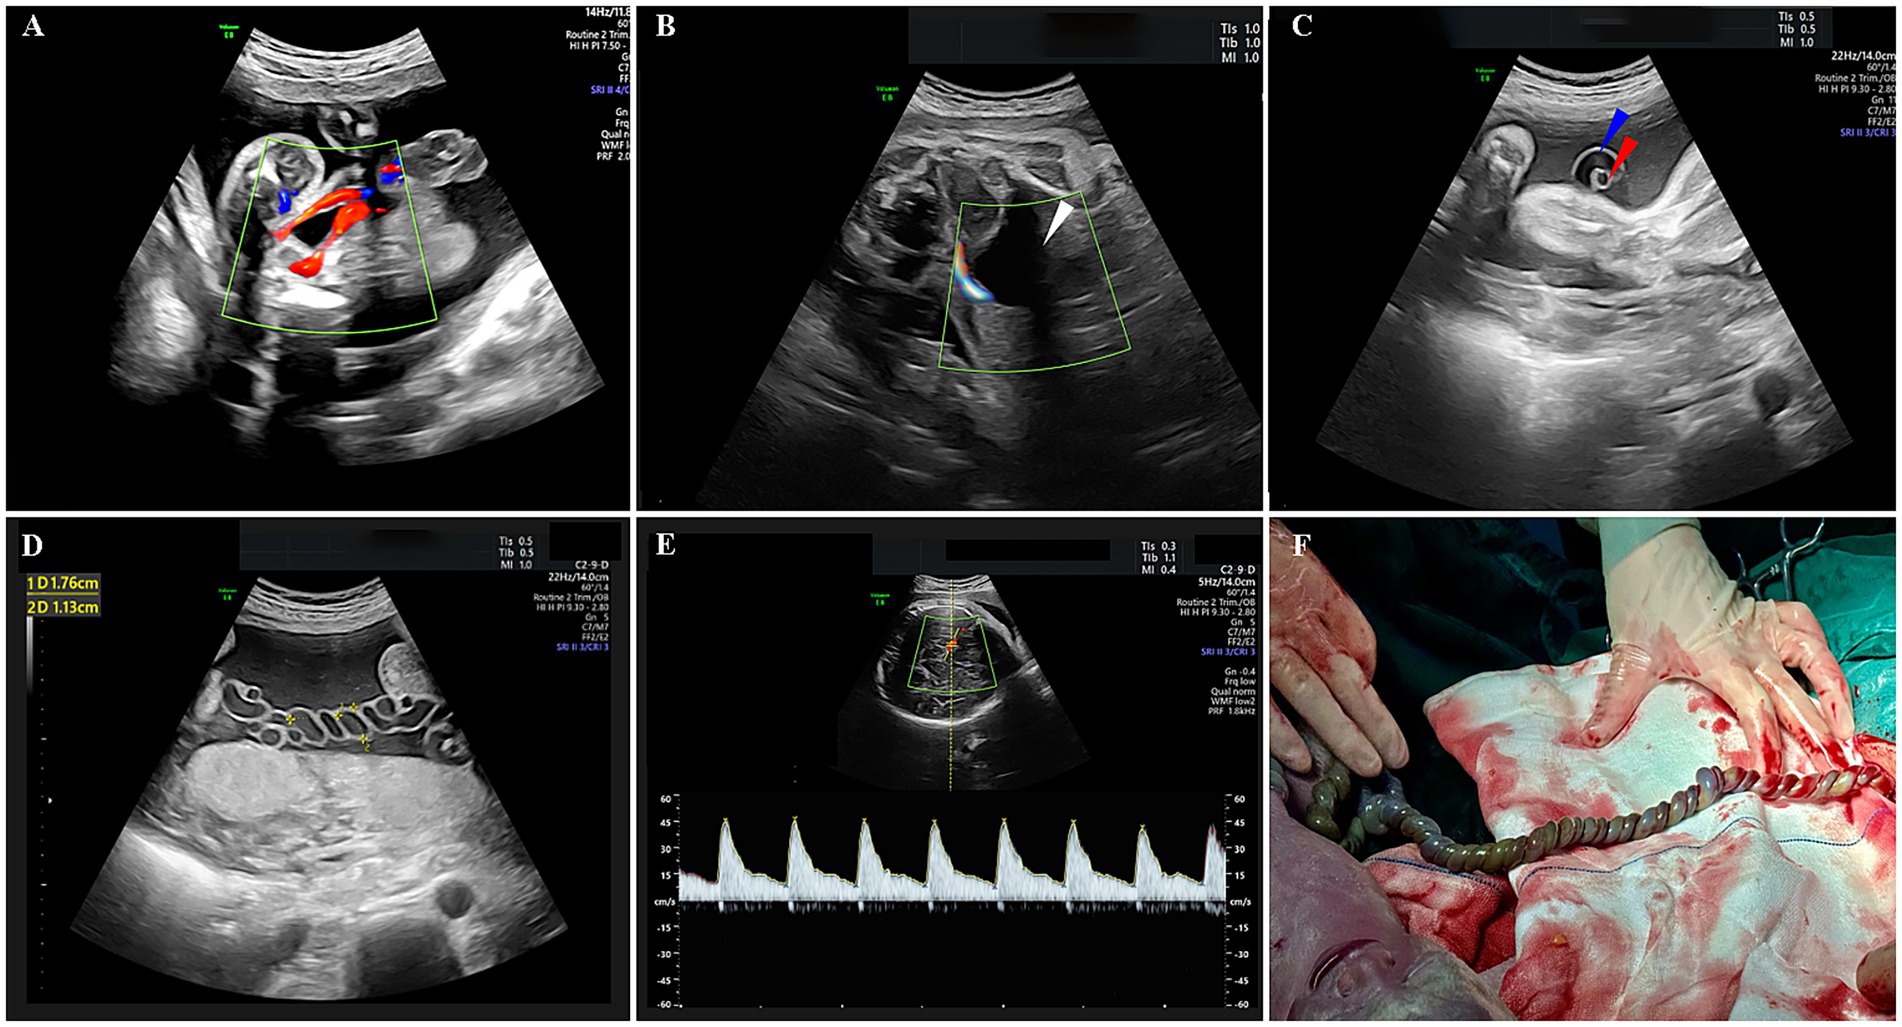

A 32-year-old woman, gravida 2 para 1, with no personal or family history of thrombosis, underwent regular prenatal care during her pregnancy. She was classified as low-risk, with a normal first-trimester screening including nuchal translucency (NT) measurement of 1.4 mm (a sonographic marker for chromosomal abnormalities like trisomy 21) (9) and a mid-trimester four-dimensional ultrasound at 23 3/7 weeks showing a normal fetus with two umbilical arteries (Figure 1A). A 75-g oral glucose tolerance test was within normal limits, and coagulation profiles were unremarkable. At 29 3/7 weeks, an external hospital ultrasound suggested a SUA and fetal growth lagging by 1 week, but no intervention was initiated as fetal movements were normal. At 32 1/7 weeks, she presented to our hospital, where ultrasound revealed a SUA (Figures 1B,C), FGR (below the 10th percentile for gestational age), and abnormal umbilical cord coiling (Figure 1D). Although current ultrasound showed no definitive signs of UAT, the confirmed presence of two umbilical arteries at 23 3/7 weeks (Figure 1A) led to admission with provisional diagnosis of UAT and FGR. Laboratory tests, including coagulation profiles, autoimmune antibodies, and platelet counts, were normal. Treatment included low-molecular-weight heparin, dexamethasone for fetal lung maturation, and magnesium sulfate for neuroprotection. Repeat ultrasound 2 days later showed reduced umbilical artery flow, decreased middle cerebral artery pulsatility index (PI) (1.52 < 10th percentile) (10) (Figure 1E), and hypercoiled cord. An urgent cesarean section was performed. After delivery, a SUA was observed, with hypercoiling of the umbilical cord and localized color changes (Figure 1F). The umbilical cord exhibited over 50 coils and measured about 90 cm in length (umbilical coiling index 0.57 coils/cm, >0.319 diagnostic threshold for hypercoiling) (11) (Figure 1F). The placenta exhibited a circumvallate morphology with a marginally inserted umbilical cord. The male newborn, weighing 1,490 g, achieved Apgar scores of 10/10 at 1 and 5 minutes. He was subsequently transferred to the neonatal intensive care unit (NICU) due to respiratory distress syndrome (RDS), very low birth weight (VLBW), and hypoglycemia. Arterial blood gas analysis showed a pH of 7.27 and PO2 of 53 mmHg. The infant received non-invasive positive pressure ventilation for 3 days, high-flow nasal cannula for 2 days. Moreover, the infant developed hyperbilirubinemia and was treated with phototherapy for jaundice. He was discharged after 27 days with a weight of 2,300 g, showing no complications. Placental pathology confirmed thrombosis in one umbilical artery with muscular necrosis and luminal occlusion (Figure 2A), along with hypercoiling (Figure 2B). Follow-up assessments indicated normal developmental progress in the infant, and no abnormalities were observed in his mother. During postnatal consultations, the mother expressed gratitude, stating: “I’m recovering very well and deeply appreciate the expert care we received throughout this challenging pregnancy.” The timeline of ultrasound findings and clinical interventions during the pregnancy is illustrated in Figure 3.

Figure 1

Prenatal ultrasound and post-delivery gross findings. (A) Prenatal ultrasound showing umbilical artery blood flow on both sides of the bladder at 23 3/7 weeks of gestation. (B) Prenatal ultrasound showing umbilical artery blood flow on only one side of the bladder at 32 1/7 weeks of gestation. (C) One umbilical artery with umbilical vein in cross-section. (D) Hypercoiling of the umbilical cord. (E) Blood flow of the middle cerebral artery. (F) Hypercoiled umbilical cord with focal discoloration. An umbilical cord measuring 90 cm in length with over 50 coils was observed. The white arrow indicates the bladder, the blue arrow indicates the umbilical vein, and the red arrow indicates the umbilical artery.